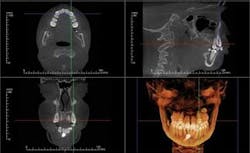

Anatomage is at the forefront of this "Dynamic CBCT" with its ability to superimpose two CBCT scans to visualize actual changes over time or projected changes with modeling simulations (Figure 4).